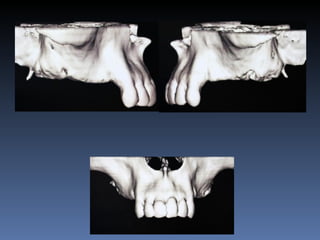

BOX 3 Kátia MariaCavicchia Idade – 43 anos Sexo – Feminino Raça – Caucasiana ASA – II Data- 29-04-2012 Diagnóstico: Desdentado parcial bilateral posterior da mandíbula. Plano de tratamento: Reabilitação bilateral posterior mandibular com instalação de 6 implantes endo- ósseos, para reabilitação protética fixa.

• 158.

Zona 4.4, 4.5,4.6 Zona 3.5, 3.6, 3.7